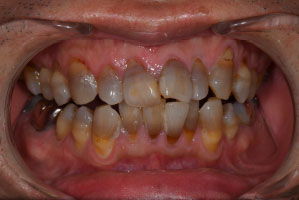

歯列矯正・インレー・クラウン症例

前歯が黒っぽいのが気になる、

悪いところは全部治したい

年齢 54代女性

主訴 歯をきれいにしたい

症例写真(治療前)

担当医師所見

治療前:

八重歯が目立ちます。また銀歯もおおく、見た目が気になります。虫歯も散見できます。

症例写真(治療後)

矯正装置をつけています。だんだん八重歯が動いてきているのがわかります。今回のケースでは、抜歯を行わずに矯正ができました。

治療後:

矯正治療と虫歯の治療すべて終わったときの写真になります。見た目も最初の頃とは全く違いますし、お口の中もすごく綺麗です。

治療

方針

まずは虫歯の治療を行い、被せ物をする部分は仮歯をいれて矯正を行う。矯正終了後、仮歯の部分を最終的な被せ物に変えていく。また気になっていた銀歯もセラミックに変えて終了となった。

内容

セラミックインレー、オールセラミックプレミアム、矯正